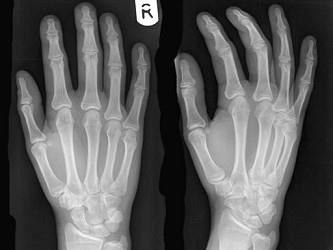

女,请根据其正常手的影像图像,判断其最可能的年龄 ( )A、47岁左右B、37岁左右C、57岁左右D、17岁左右E、67岁左右

问题 女,请根据其正常手的影像图像,判断其最可能的年龄 ( )

选项 A、47岁左右 B、37岁左右 C、57岁左右 D、17岁左右 E、67岁左右

答案 D